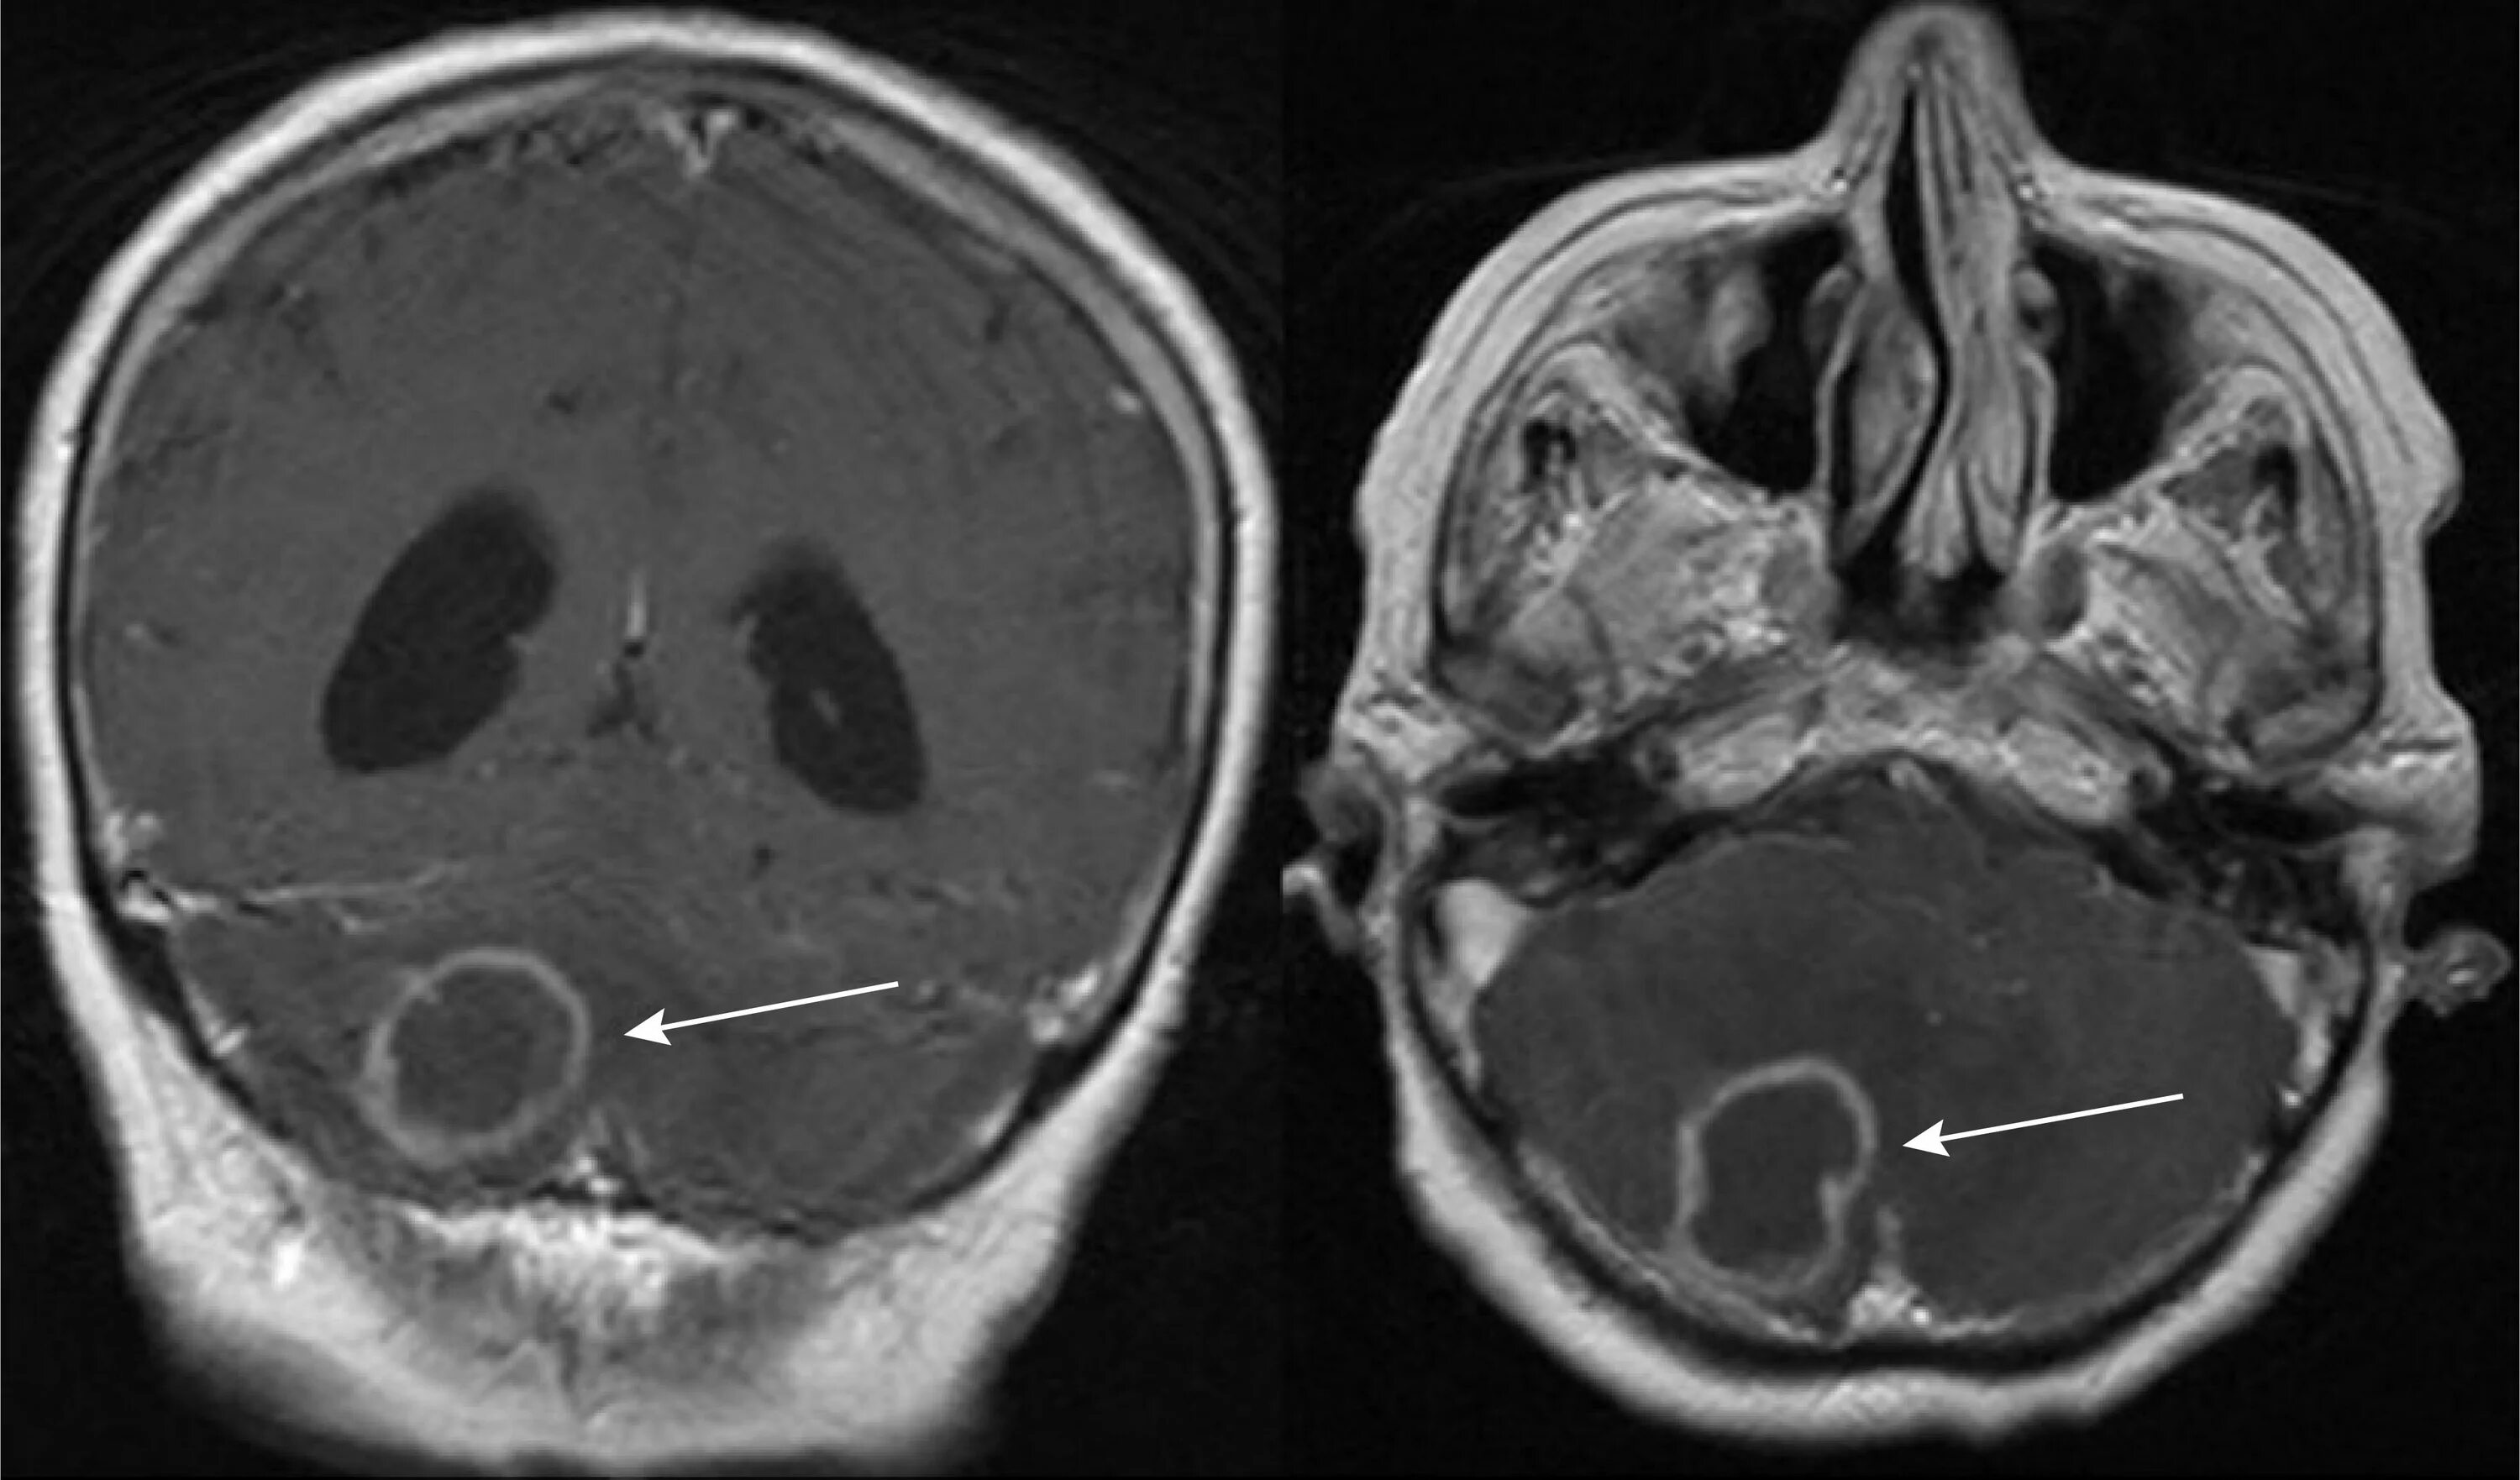

Мрт головного мозга мосто мозжечкового угла